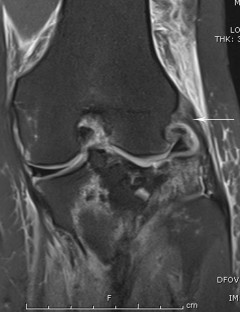

Fig. 2